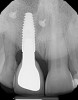

(6.) Pretreatment periapical radiograph.

Figure 6